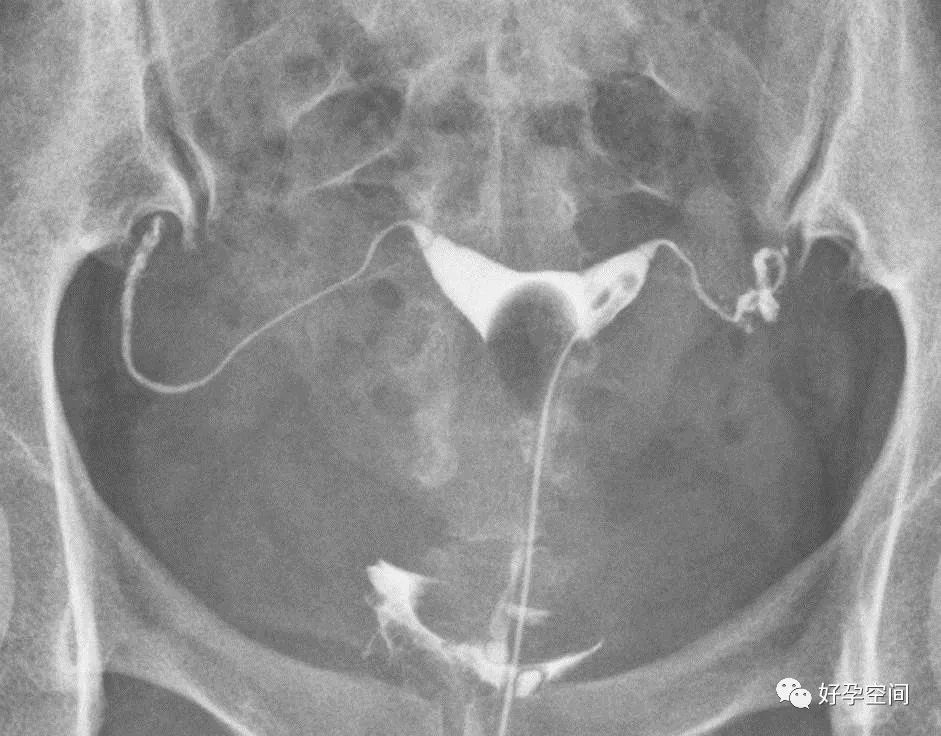

子宫相

输卵管相